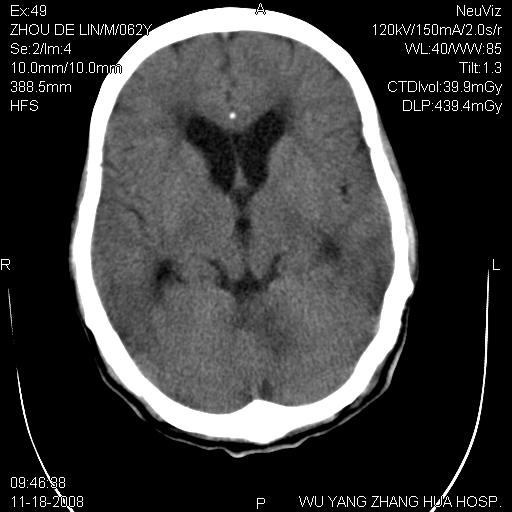

患者近段时间偶有头晕,无其他不适。既往有糖尿病病史。

小脑中线区见一类圆形混杂密度影,四脑室受压变形,其后方见一边界清楚的囊性低密度影,幕上脑室扩张。小脑中线区肿瘤,儿童多见于髓母细胞瘤,成人多见于胶质瘤。

诊断:小脑胶质瘤可能性大。建议增强扫描

小脑囊实性占位病变、脑室系统积水扩张、脑肿胀。

小脑囊实性占位病变、脑室系统积水扩张,建议增强

小脑囊实性占位病变、脑室系统积水扩张

1)小脑蚓部(偏左侧)占位性病变;不排除转移瘤可能。建议行进一步检查。2)脑积水。